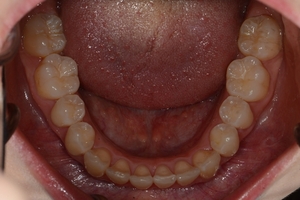

ガタガタとした歯並びや八重歯(叢生)CASE72